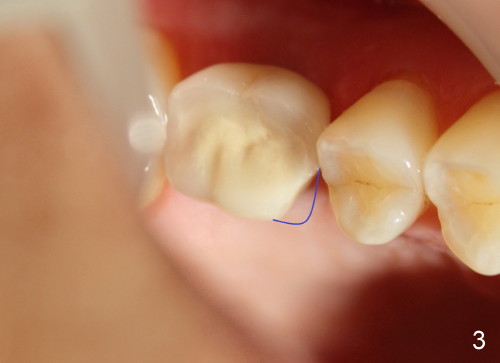

Three years after new crown fabrication, the mesiolingual cusp of the PFM fractures (Fig.3 blue outline). This time, the patient has no problem eating, since the contact is not lost. X-ray shows that the mesial portion of the porcelain is not supported by metal framework (Fig.4 ^). Our treatment plan is first to restore the missing tooth #18.